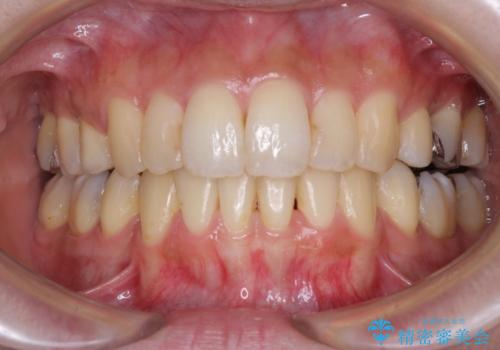

[ 先天性の前歯欠損 ] 矯正とインプラントの包括治療

![[ 先天性の前歯欠損 ] 矯正とインプラントの包括治療の症例 治療後](https://seimitsushinbi.jp/wp/wp-content/uploads/2022/12/e325c4369c68ab4ded73824110858d06-500x350.jpg?v=1671606193)